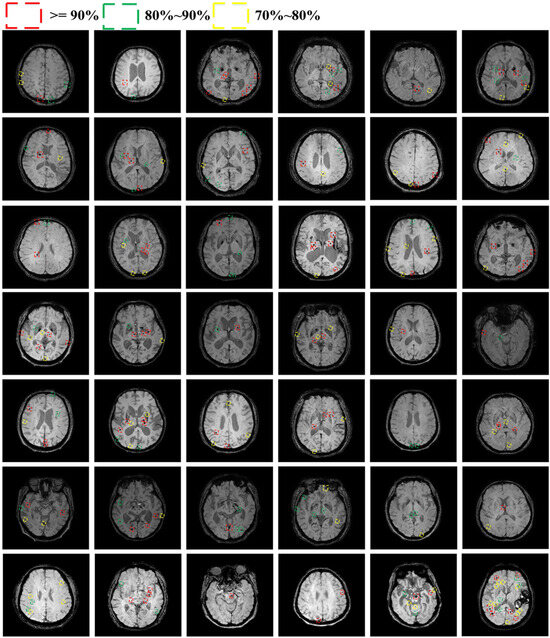

4.3.1. Detection Performance of CMBs

4.3.2. Classification Performance of CMBs